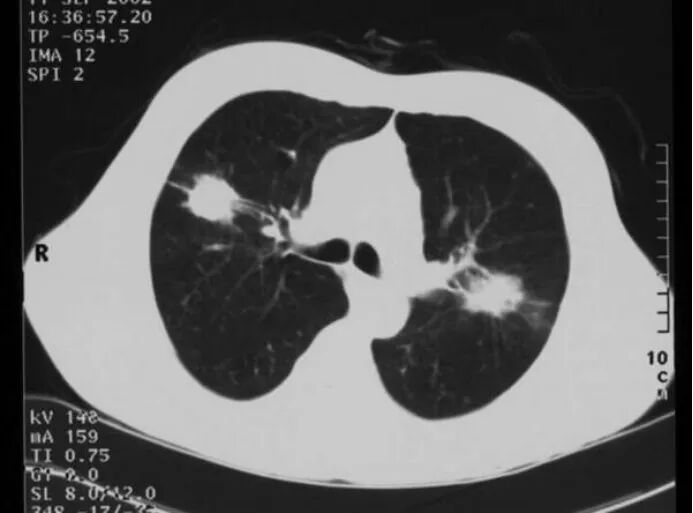

一眼看懂PET-CT原理作者: 田耕医生 肿瘤科主任医师 PET-CT的全称叫正电子发射断层显像-X线电脑体层成像,实际上是由PET和CT两种设备组合而成,即一个过程同时做了PET和CT两种检查。同时提供解剖显像和功能显像,是目前影像诊断技术中最为理想的结合。特别是在肿瘤的诊断、分期、疗效评估等方面发挥重要的作用。CT检查已被广泛应用,其原理大家已经有所了解。那么PET-CT的原理是什么?PET-CT的原理包括两部分:1.PET的显像原理;2.PET与CT的图像融合。下面我们先来看PET的显像原理。 为了更好的说明这个问题,从下面这个例子入手可能更好理解:现在有两颗黄豆,一颗是炒熟的,但颜色没变,另一颗没炒,你有什么方法把它们鉴别开吗? 图一:你能说出哪一个是炒熟的黄豆吗? 显然,从颜色、形状、大小、质地、轻重等方面无法将它们区分开,但它们是有本质区别的:炒过的黄豆是没有活性的,而没炒的黄豆是有生物活性的,当给予适当的温度和水,它会长成豆芽。因此它们的区别在于是否有活性: 图二:炒过的黄豆是没有活性的,是“死”的,而没炒的黄豆是有生物活性的。 如果有一种方法能够鉴别是否有活性,就能够将它们区别开。 PET就是这样一种检查,可以检查出不同病灶的代谢活性,从而为鉴别诊断提供重要资讯。恶性肿瘤有一个共同的特性就是代谢活性非常高。它是人体内的「强盗」,掠夺性的摄取营养,往往是肿瘤患者越来越瘦,可肿瘤却越长越大。葡萄糖是人体细胞(包括肿瘤细胞)能量的主要来源之一,因此恶性肿瘤摄取的葡萄糖远远多于其它正常组织。利用这一特性,在葡萄糖上标记上带有放射活性的元素氟-18作为显像剂18F-FDG,将此显像剂注入静脉内,在体内回圈,恶性肿瘤摄取的18F-FDG远多于其它组织,因此,肿瘤细胞内可积聚大量18F-FDG,经PET显像可以检测到体内18F分布情况从而显示肿瘤的部位、形态、大小、数量及肿瘤内的放射性分布。 我们来看一个临床应用的例子:一位患者因咳嗽咳痰就诊,痰中查见癌细胞,医生给他做了胸部CT,结果如图三: 图三:哪个病灶是癌?两个病灶都是癌? CT看到这位患者左右肺各有一个占位元病灶,增强扫描也未能提供足够的信息来判断出每个病灶的性质。于是这个患者的诊断有下列几种可能:1.右肺癌,左肺良性占位病变,如无远处转移,可能需要行右肺手术;2.左肺癌,右肺良性占位元病变,可能需要行左肺手术;3.双肺均为癌,则要双肺同时治疗。可见弄清楚诊断是多么重要,错误的诊断意味着错误的治疗。纤维支气管镜和肺穿刺活检是临床常用的方法,但如果能有一种无创、简便的方法将两个病灶鉴别开来该多好。 这位患者做了PET检查,结果如图四: 图四:左侧病灶(红色箭头,右肺病灶)是高代谢病灶,考虑为癌。 可以看到图中左侧的病灶(红色箭头,右肺病灶)呈现较深的黑色,表示摄取了较多的18F-FDG,是一个高代谢病灶,考虑为恶性肿瘤;右侧的病灶(蓝色箭头,左肺病灶)颜色很淡,表示摄取18F-FDG不多,是一个低代谢病灶,考虑为良性病变。患者痰中已查到癌细胞,因此,该患者的诊断已经明确:右肺癌,身体其它部位未见转移。最后接受了右肺手术治疗。 上一篇肾移植术后患者需知下一篇从微生物角度看医学实践 |